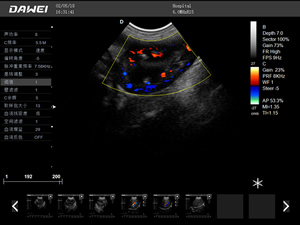

·支持彩色多普勒、頻譜多普勒、能量多普勒、連續多普勒等成像技術